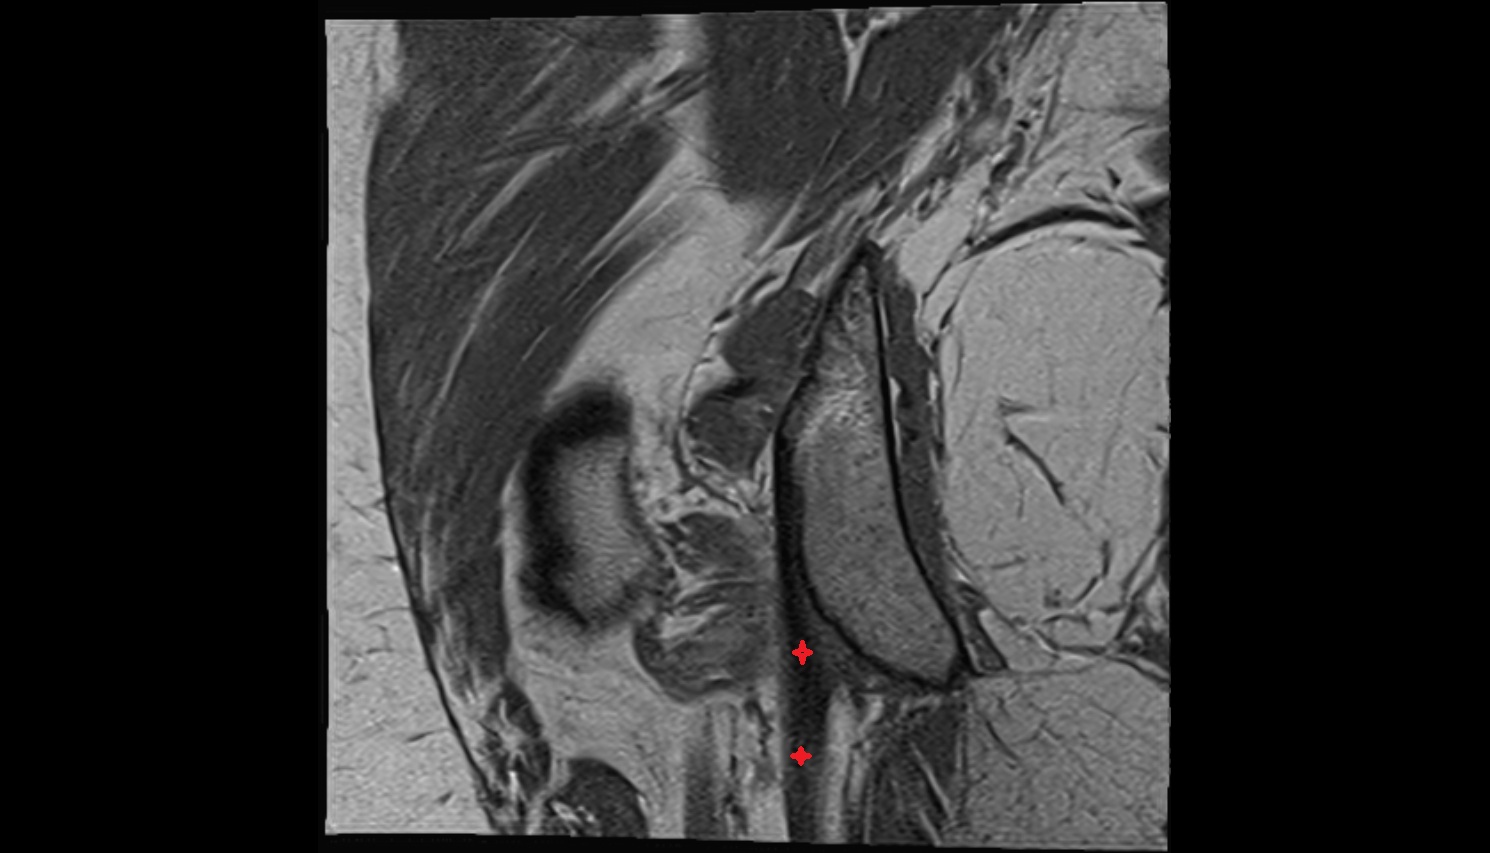

- Hip joint